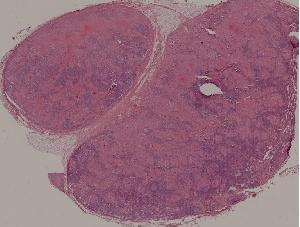

89. Tuberculous lymphadenitis